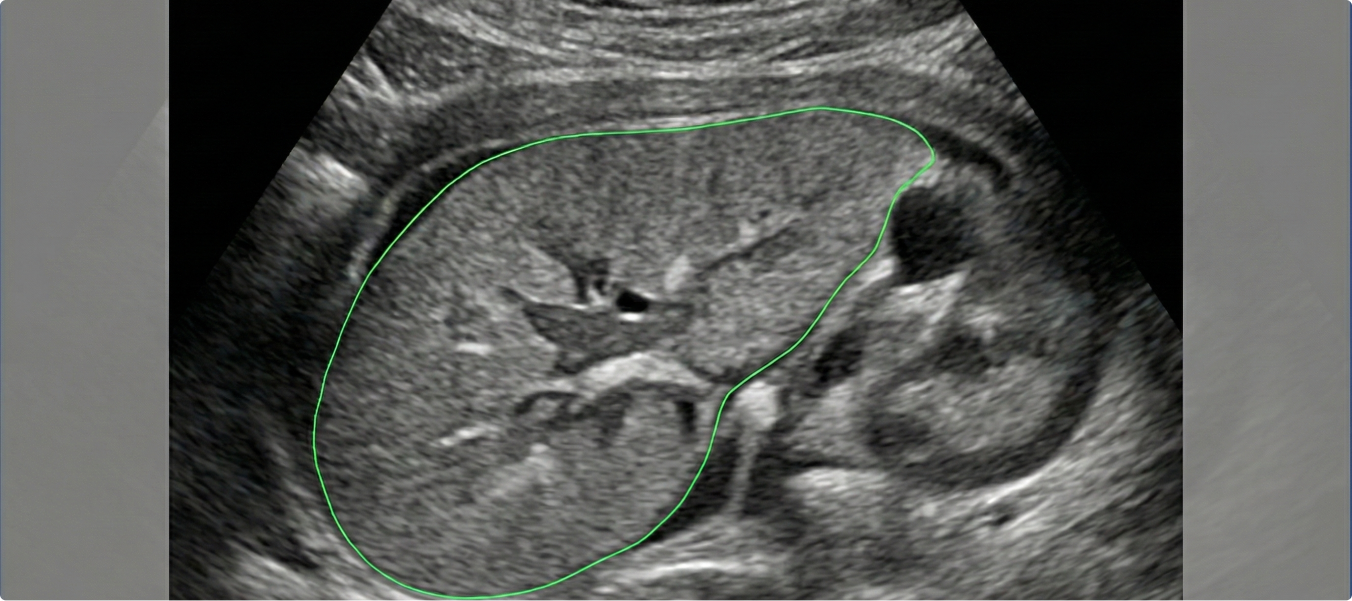

For healthcare automation, high-accuracy polyline annotations were required on ultrasound-based MRI datasets. The main challenge was ensuring precision while maintaining speed across medical images.

• Used 2D polyline annotation for precise boundary mapping.

• Applied strict QA measures to maintain near-perfect accuracy.

• Supported automation goals for healthcare AI models.

• Annotated a total of 1,000 ultrasound MRI images with precise details.

• Average annotation time was 3 minutes per image, enabling efficient throughput.

• Achieved 98.7% accuracy, delivering near-perfect datasets for automation.